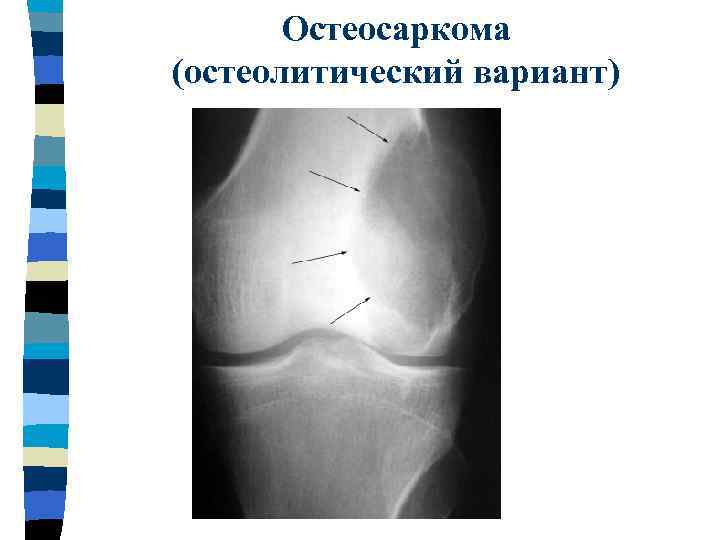

Остеосаркома (остеолитический вариант)